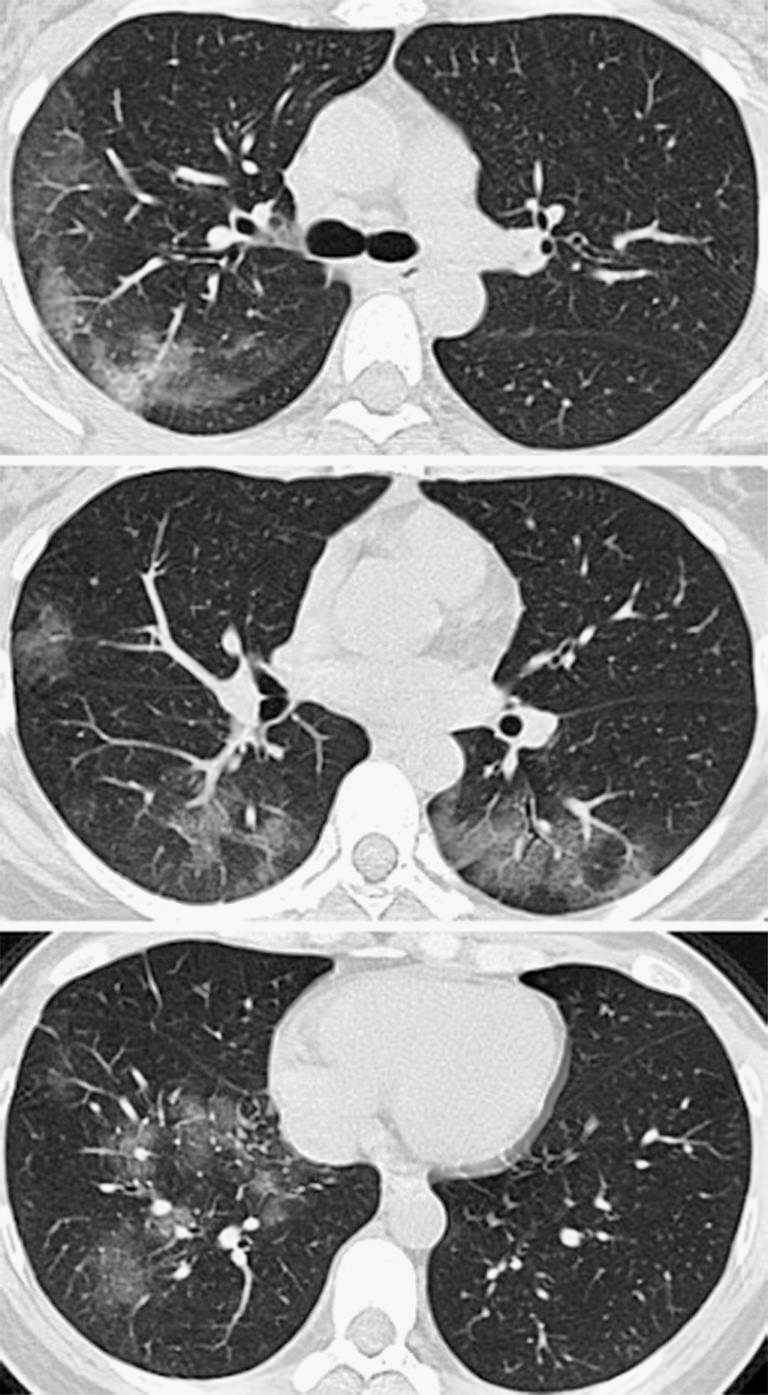

Zistili tam zarážajúcu skutočnosť. Mesiac sledovali pacientov, ktorí podstúpili RT-PCR test aj hrudníkové CT (computerová tomografia). Presnosť diagnostiky COVID-19 pomocou CT pľúc je až 98%. Čítate dobre, to číslo sa blíži istote.

Šokujúca je skutočnosť, ktorú zistili Číňania vo Wu-hane okolo 10.februára 2020 - že u pacientov, ktorí boli negatívne testovaní PCR krvným testom - bolo 75% pozitívnych pri CT vyšetrení...Použitie tejto diagnostiky znamenalo razantný nárast počtu zistených ochorení - viď obrázok vyššie (a tiež množstvo konšpirácii že Čína maskovala skutočný počet ochorení...)

Okamžite však na to zareagovali a vyvinuli technológiu, ktorá dokáže zmeny spôsobené koronavírusom v CT - snímkach namerať do 15 sekúnd. Preto čínski vedci a lekári vedci navrhli, aby sa CT vyšetrenie stalo primárnym skríningovým nástrojom v diagnostike COVID-19. Stačí iba 15 sekúnd merania a špeciálny program vyhodnotí snímku za 15 minút a máme výsledok. Práve preto zaznamenali čínske štatistiky v tých dňoch radikálny skok zhruba o 10 000 chorých hore - v dôsledku CT meraní!

Ak aj nie táto technológia dostupná, rádiológ na snímku pľúc, taktiež vidí okamžite zmeny na pľúcach spôsobené COVID-19. Nemusíme čakať hodiny, dni na výsledky krvných testov.